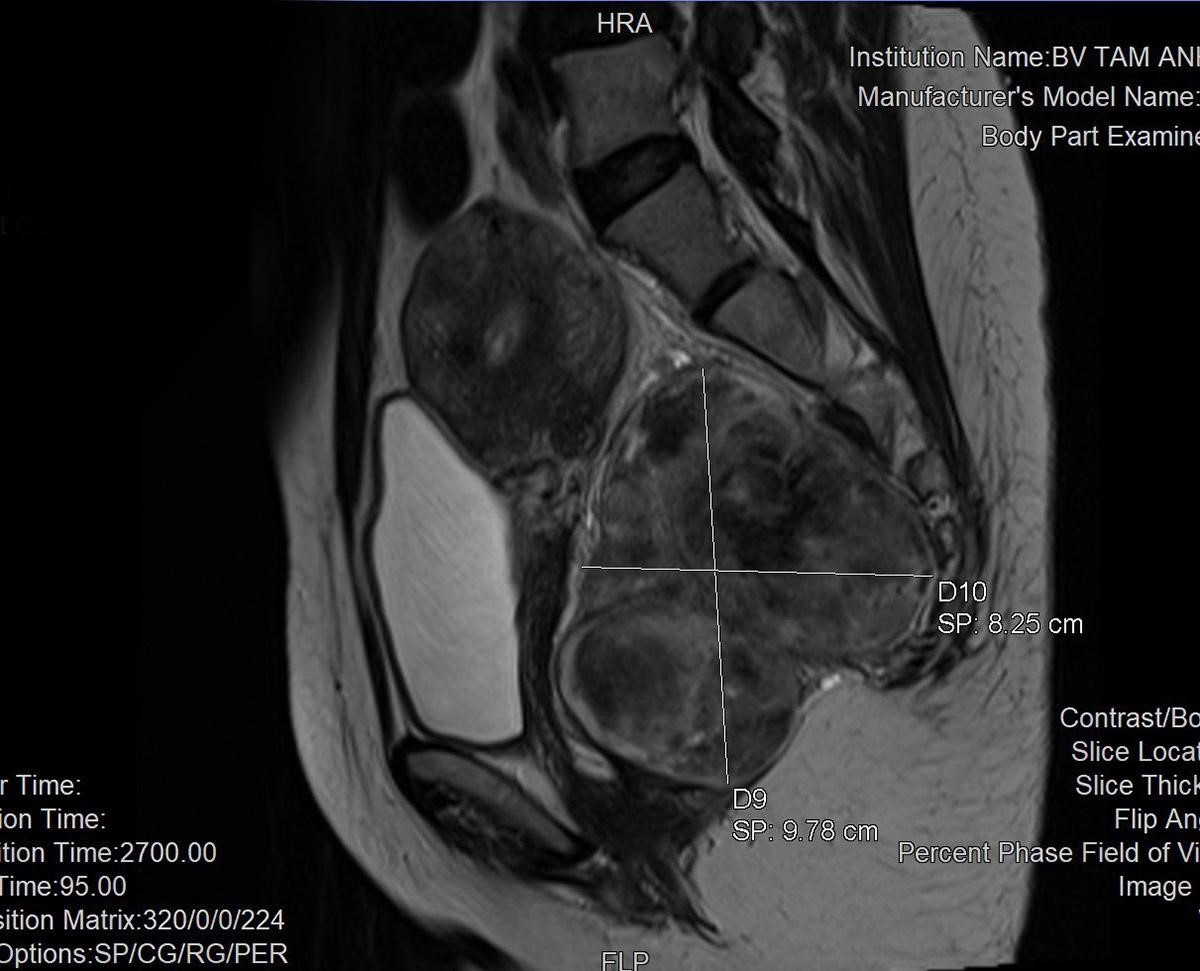

Kết quả chụp MRI vùng chậu tại Trung tâm Chẩn đoán hình ảnh cho thấy khối u có kích thước khoảng 8-10 cm nằm ở vị trí khó phẫu thuật, sau trực tràng và trước xương cùng cụt. Một phần khối u được nhận định có vẻ đã xâm lấn vào mạch máu trước xương cùng cụt.

Hình ảnh khối u hiển thị rõ trên phim chụp MRI. Ảnh: BVCC.